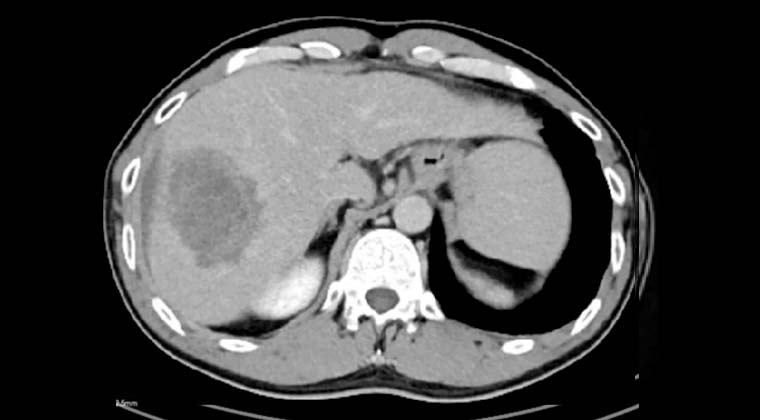

Наблюдение и исход: Контрольные обследования показали выраженное уменьшение размеров опухоли и регресс опухолевого тромба воротной вены. По данным визуализации был отмечен некротический ответ очагов.

После MDT-оценки и подтверждения возможности хирургического вмешательства было выполнено оперативное удаление некротизированной опухоли. По данным патоморфологического исследования подтверждён некроз опухоли. Общее состояние пациента постепенно улучшилось, качество жизни повысилось.

(Визуализационные исследования после лечения иттрием-90)